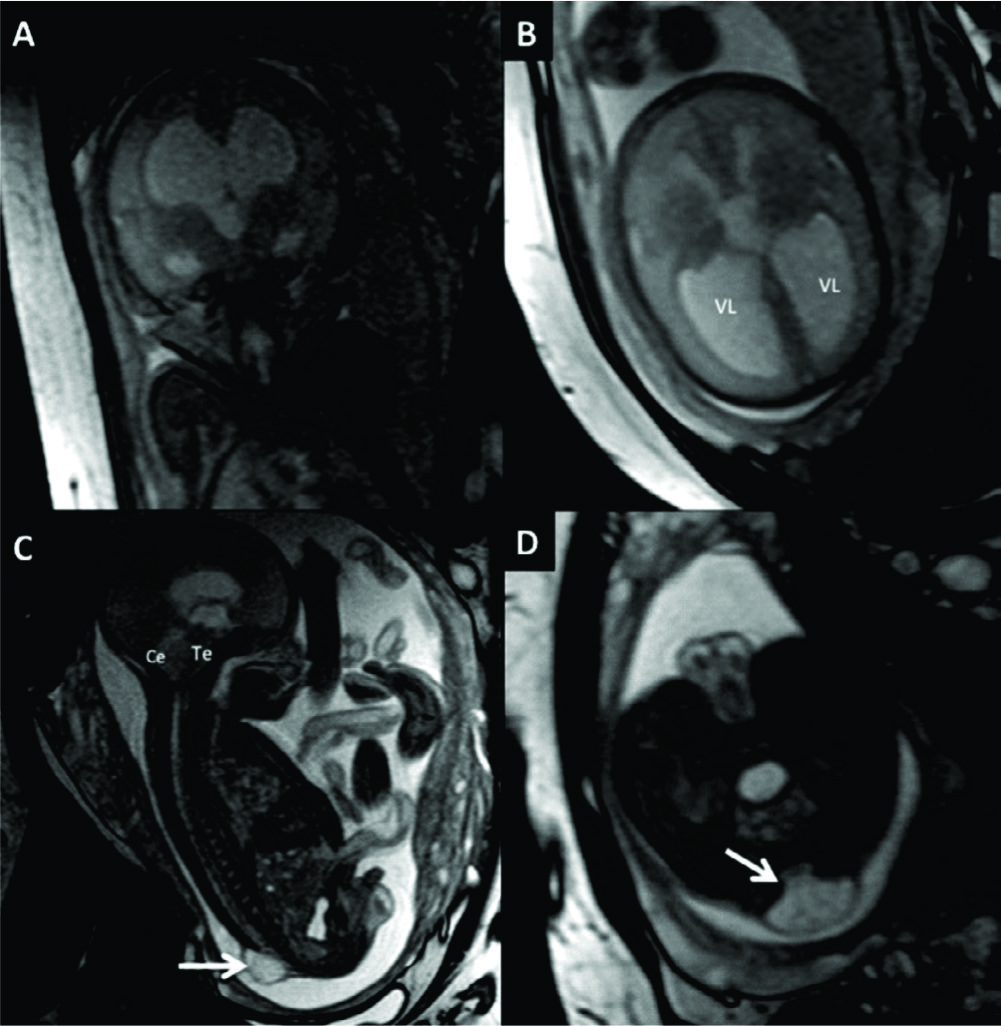

Figura 4

RM Fetal Hidrocefalia por Estenosis del acueducto.

Se presentan 2 casos de fetos con hidrocefalia (HCF) por estenosis del acueducto. El primer caso se presenta con HCF leve/moderada (A sagital y B axial) donde puede observarse la dilatación ventricular supra-tentorial con IV ventrículo normal lo que orienta al diagnóstico de estenosis del acueducto.

En C se muestra imagen sagital del 2º caso con HCF severa y ausencia de señal en el acueducto de Sylvio lo que orienta al diagnóstico (è). AV: Atrio ventricular

CC: cuerpo calloso

Te: Tronco encefálico

Ce: Cerebelo

Figura 7

RM Fetal Holoprosencefalia.

RMf a las 28 semanas referido por estudio ecográfico para confirmación de holoprosencefalia. En el plano coronal (A) se identifica la cavidad ventricular única con manto cerebral periférico adelgazado y la característica masa intermedia (MI) por la ausencia de división de ambos tálamos.

En el plano axial (B) los hallazgos son similares con ausencia de estructuras de la línea media como cisura inter-hemisférica u hoz cerebral. Te: Tronco encefálico